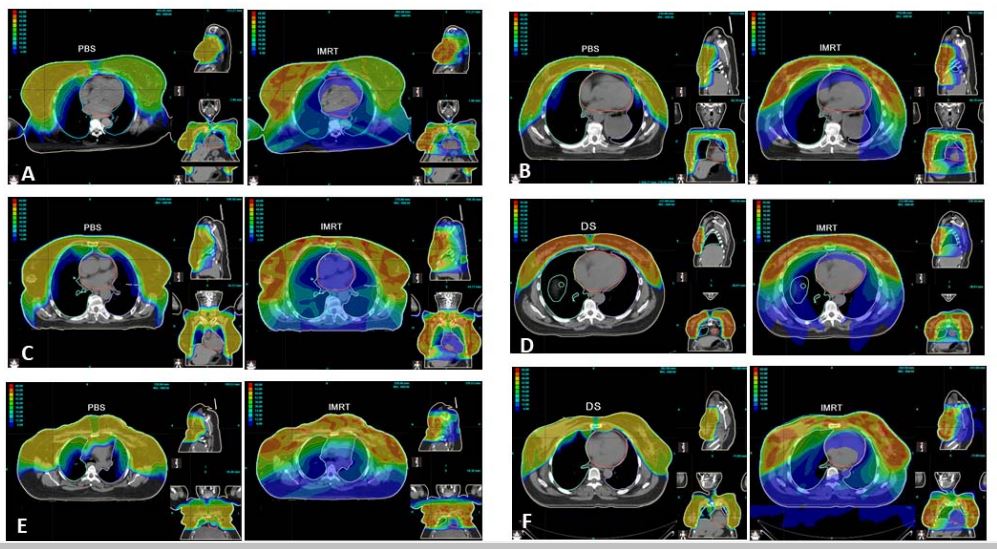

Substantial dose reductions to multiple OAR while maintaining target coverage make #protontherapy the preferred modality for bilateral breast cancer treatment - learn more: bit.ly/IJPT-Spring-20… #CancerResearch #cancer #breastcancerawareness @UFProtonTherapy

theijpt's tweet image. Substantial dose reductions to multiple OAR while maintaining target coverage make #protontherapy the preferred modality for bilateral breast cancer treatment - learn more: bit.ly/IJPT-Spring-20… #CancerResearch #cancer #breastcancerawareness @UFProtonTherapy